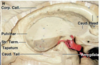

Key gyri on orbital view of frontal lobe

Gyrus rectus

Medial orbital gyrus

Anterior orbital gyrus

Posterior orbital gyrus

Lateral orbital gyrus

Key sulci on orbital surface of frontal lobe

Olfactory sulcus

Orbital sulcus